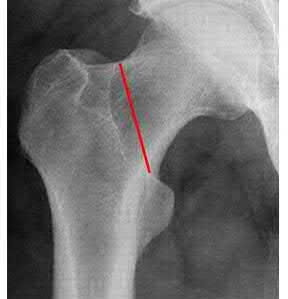

A 35-year-old-male sustains the fracture seen in Figure A. Which of the following reduction forces must be applied to the proximal fragment to correct the deformity commonly seen in these fractures?

Figure A demonstrates a displaced subtrochanteric femur fracture with an intact lesser trochanter. The pull of iliopsoas on the lesser trochanter as well as the intact external rotators and gluteal musculature results in the the proximal fragment being in a flexed and externally rotated or abducted position (the most common post operative deformity). Reduction manuevers must be biologically friendly but also counteract the flexion/abduction moment. Lundy's review article discusses evaluation and treatment of subtrochanteric fractures. The review article details the various implants often used which include 95 degrees plates, femoral reconstruction nails, or trochanteric femoral nails with interlocking options. Lundy's article discourages the use of the 135 degree screw and side plate combo due to high failure rates in these fracture patterns. Bedi et al also review treatment of these fractures and discuss common

problems of malunion, nonunion, and implant failure. The article reviews reduction techniques that are soft tissue friendly, as well as the use of appropriate implants in these fracture types.